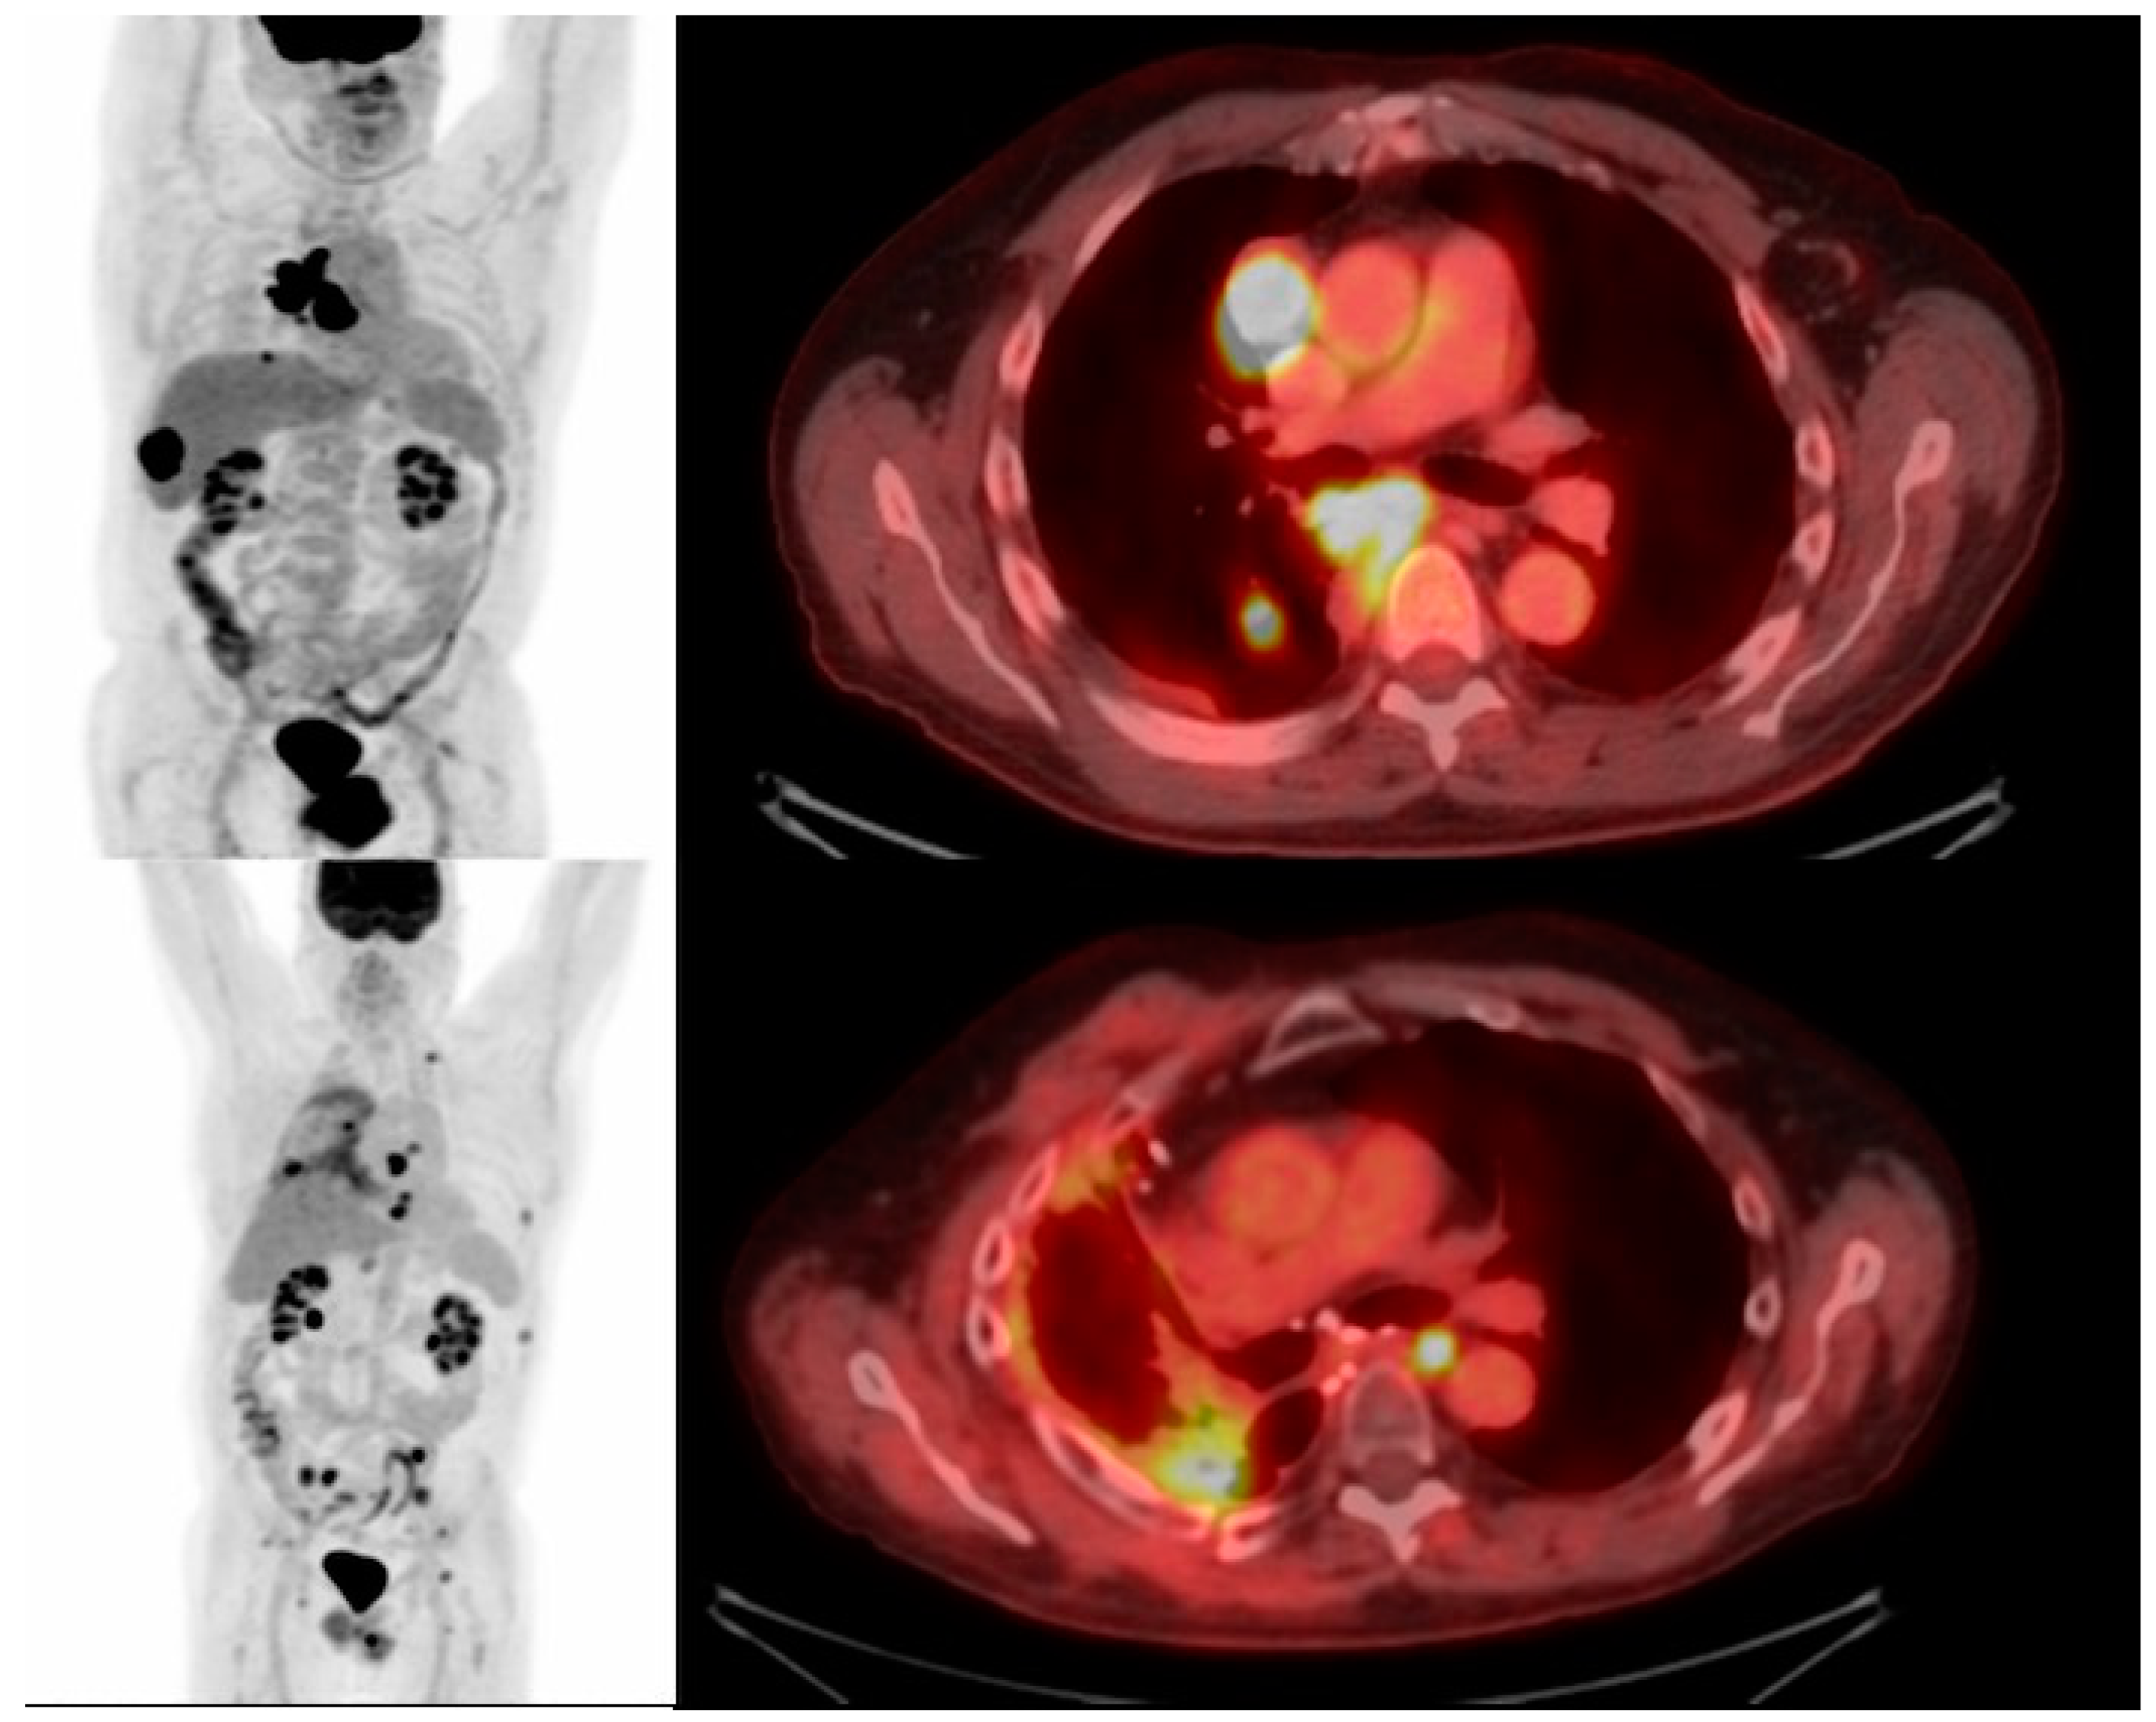

- Volpe, A.; Lang, C.; Lim, L.; Man, F.; Kurtys, E.; Ashmore-Harris, C.; Johnson, P.; Skourti, E.; de Rosales, R.T.M.; Fruhwirth, G.O. Spatiotemporal PET Imaging Reveals Differences in CAR-T Tumor Retention in Triple-Negative Breast Cancer Models. Mol. Ther. 2020, 28, 2271–2285. [Google Scholar] [CrossRef] [PubMed]

11. Imaging CAR T Cell Action